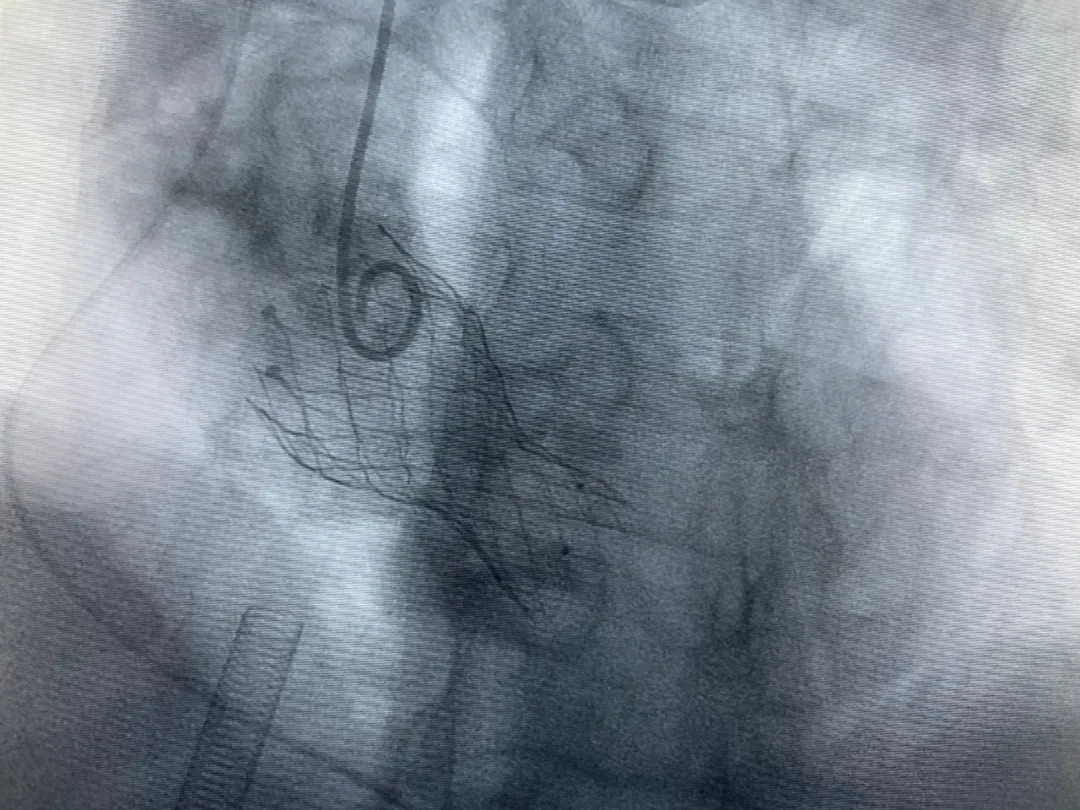

結(jié)合老人病情特點:年齡高、室壁厚、左室腔小、瓣膜鈣化嚴(yán)重,術(shù)中球囊擴張和瓣膜釋放過程有循環(huán)崩潰可能;為降低此種風(fēng)險、最大程度提高手術(shù)成功率,張金洲副院長在術(shù)前組織了由楊金保博士帶領(lǐng)的TAVR團隊多次反復(fù)溝通、討論,制定了各種應(yīng)急處理方案。最終經(jīng)過TAVR團隊的默契配合,手術(shù)歷時2小時,用20#球囊預(yù)擴張后順利植入23#主動脈瓣生物瓣膜,再次后擴后主動脈根部造影顯示:人工主動脈瓣生物瓣位置良好,瓣葉開閉正常;冠脈顯影良好。經(jīng)食道超聲顯示:主動脈瓣葉活動度良好,主動脈跨瓣壓差約35mmHg,未見瓣周漏及明顯返流。出手術(shù)室前老人便已蘇醒,自訴憋悶癥狀完全消失。